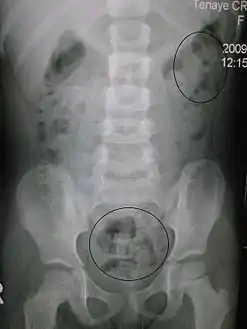

![]() تصوير أشعة يظهر إمساك لدى طفل. تشير الدوائر لمناطق تحتوي على براز (البراز يظهر بلون أبيض شفاف مُحاط بأمعاء مليئة بالغازات والتي تظهر بالأسود) تصوير أشعة يظهر إمساك لدى طفل. تشير الدوائر لمناطق تحتوي على براز (البراز يظهر بلون أبيض شفاف مُحاط بأمعاء مليئة بالغازات والتي تظهر بالأسود) | |